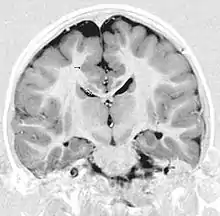

قشر مخ لایه نازکی از جنس ماده خاکستری است سطح مغز را می پوشاند.قشر مخ مرکز بسیاری از اعمالات ارادی بدن و مرکز پردازش اطلاعات حسی در مغز می باشد که چین خوردگی های این لایه به پردازش بهتر اطلاعات حسی کمک می نماید.این لایه از سلولهای عصبی مغز تشکیل شده است.علت خاکستری رنگ بودن این لایه بیرونی مخ، تجمع جسم سلولی ( پریکاریون) یاخته های عصبی تشکیل دهنده آن می باشد.ضخامت آن در نواحی مختلف مغز متفاوت است اما تقریباً در همه جا ضخامتی بین ۲ تا ۴ میلیمتر دارد.

| FMA | 61830 |